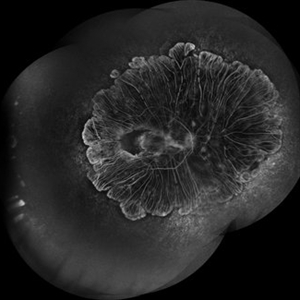

Choroideremia

A young male of 25 years, with progressive loss of vision with suspected CNVM. FFA showed 360 degree shutdown with blocked fluorescence in macular region.

Photographer: Prashant Bawankule, Sarakshi Netralaya, Nagpur, Maharashtra , India

Imaging device: Mirante ( by Nidek)

Condition/keywords: Montage of FFA in a case of choroderemia